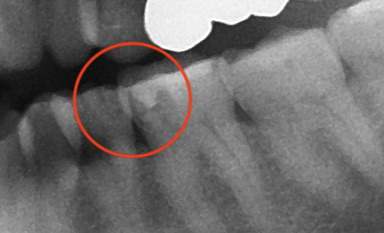

レントゲンの赤丸の部分がむし歯。